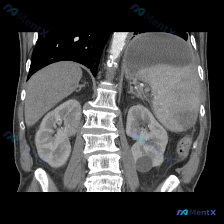

今天看到一份腹部CT的影像资料,觉得很有讨论价值,整理一下思路和大家分享。 先看影像发现 这是一张腹部CT冠状位重建(软组织窗): 1. 最突出的异常:脾脏明显肿大,占据左上腹较大空间,下缘向下延伸,但脾实质密度看起来相对均匀 2. 其他伴随发现:左肾下极有一类圆形低密度影,边缘锐利,符合单纯性肾囊...